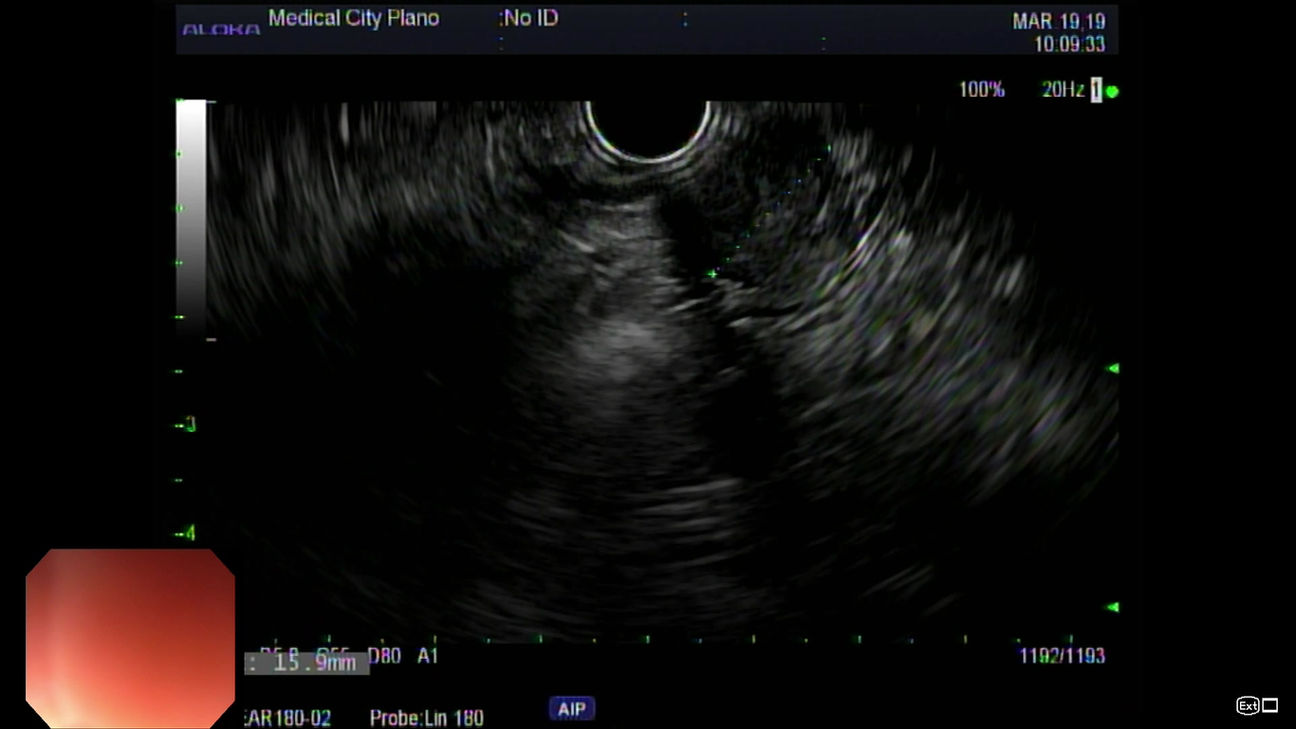

Endoscopic Video Library

Dr. Akerman provides first-rate endoscopy, colonoscopy Plano, hemorrhoid treatment Plano, and more. On this page, you'll find informative videos detailing the procedures offered as well as fascinating endoscopic findings. Follow along as Dr. Akerman provides an inside look at delivering the best possible digestive health care to patients in the Plano and Dallas communities. With his extensive experience, personalized care, and state-of-the-art endoscopy suite, it's no wonder patients seeking the best GI in Dallas choose Dr. Akerman time and again.